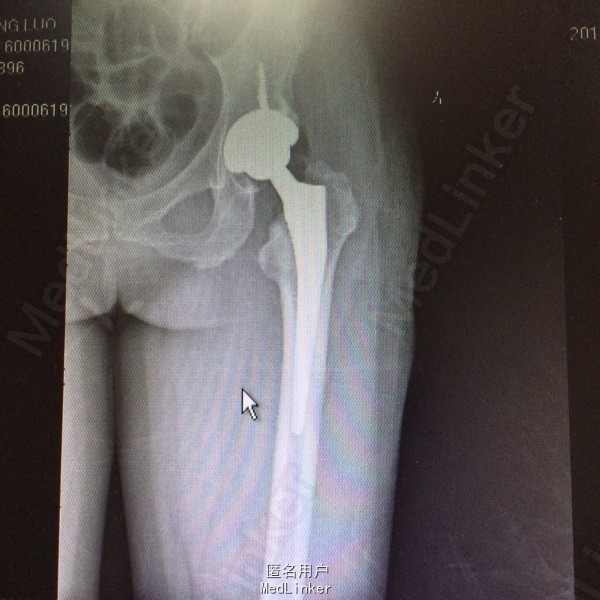

左侧人工髋关节置换术 扶乖部分负重功能锻炼,不侧身,不盘腿,不直腿抬高。不深蹲 ,指导下功能锻炼促进肢体功能恢复,避免僵硬,继续预防血栓治疗。